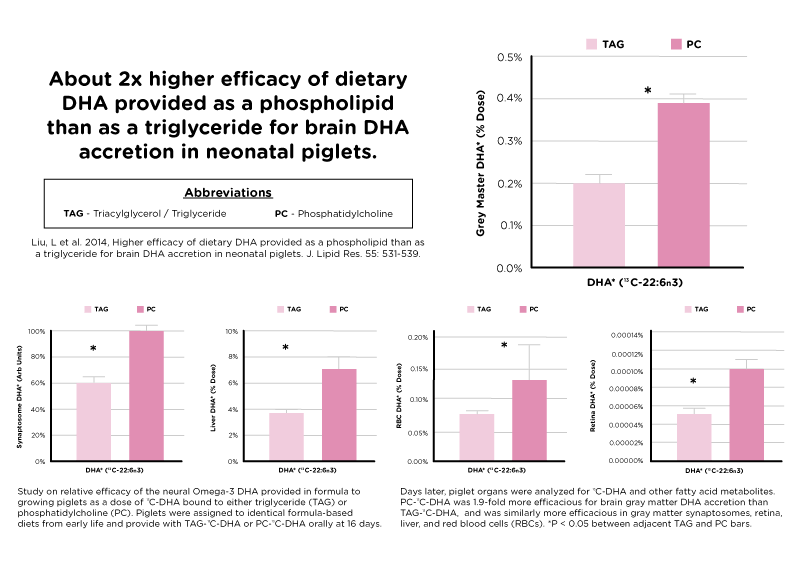

Because omega-3 makes up the building blocks of the brain and retina, and phospholipids boost the absorption!

It is a fish oil supplement that is rich in phospholipids form of omega-3 fatty acids; particularly DHA-rich phospholipids. PRISTIN® MOPL™ also comes with natural source of choline, which is known to be very beneficial for neurodevelopment. It provides more than two times better DHA and EPA absorption for a boost for your baby’s cognitive growth and development.

This enables higher absorption of omega-3 by our cells—up to SIX TIMES! Instead of purchasing ordinary omega-3 that is not being taken up by your cells, get yourself one that your body will use and not flush out quickly.